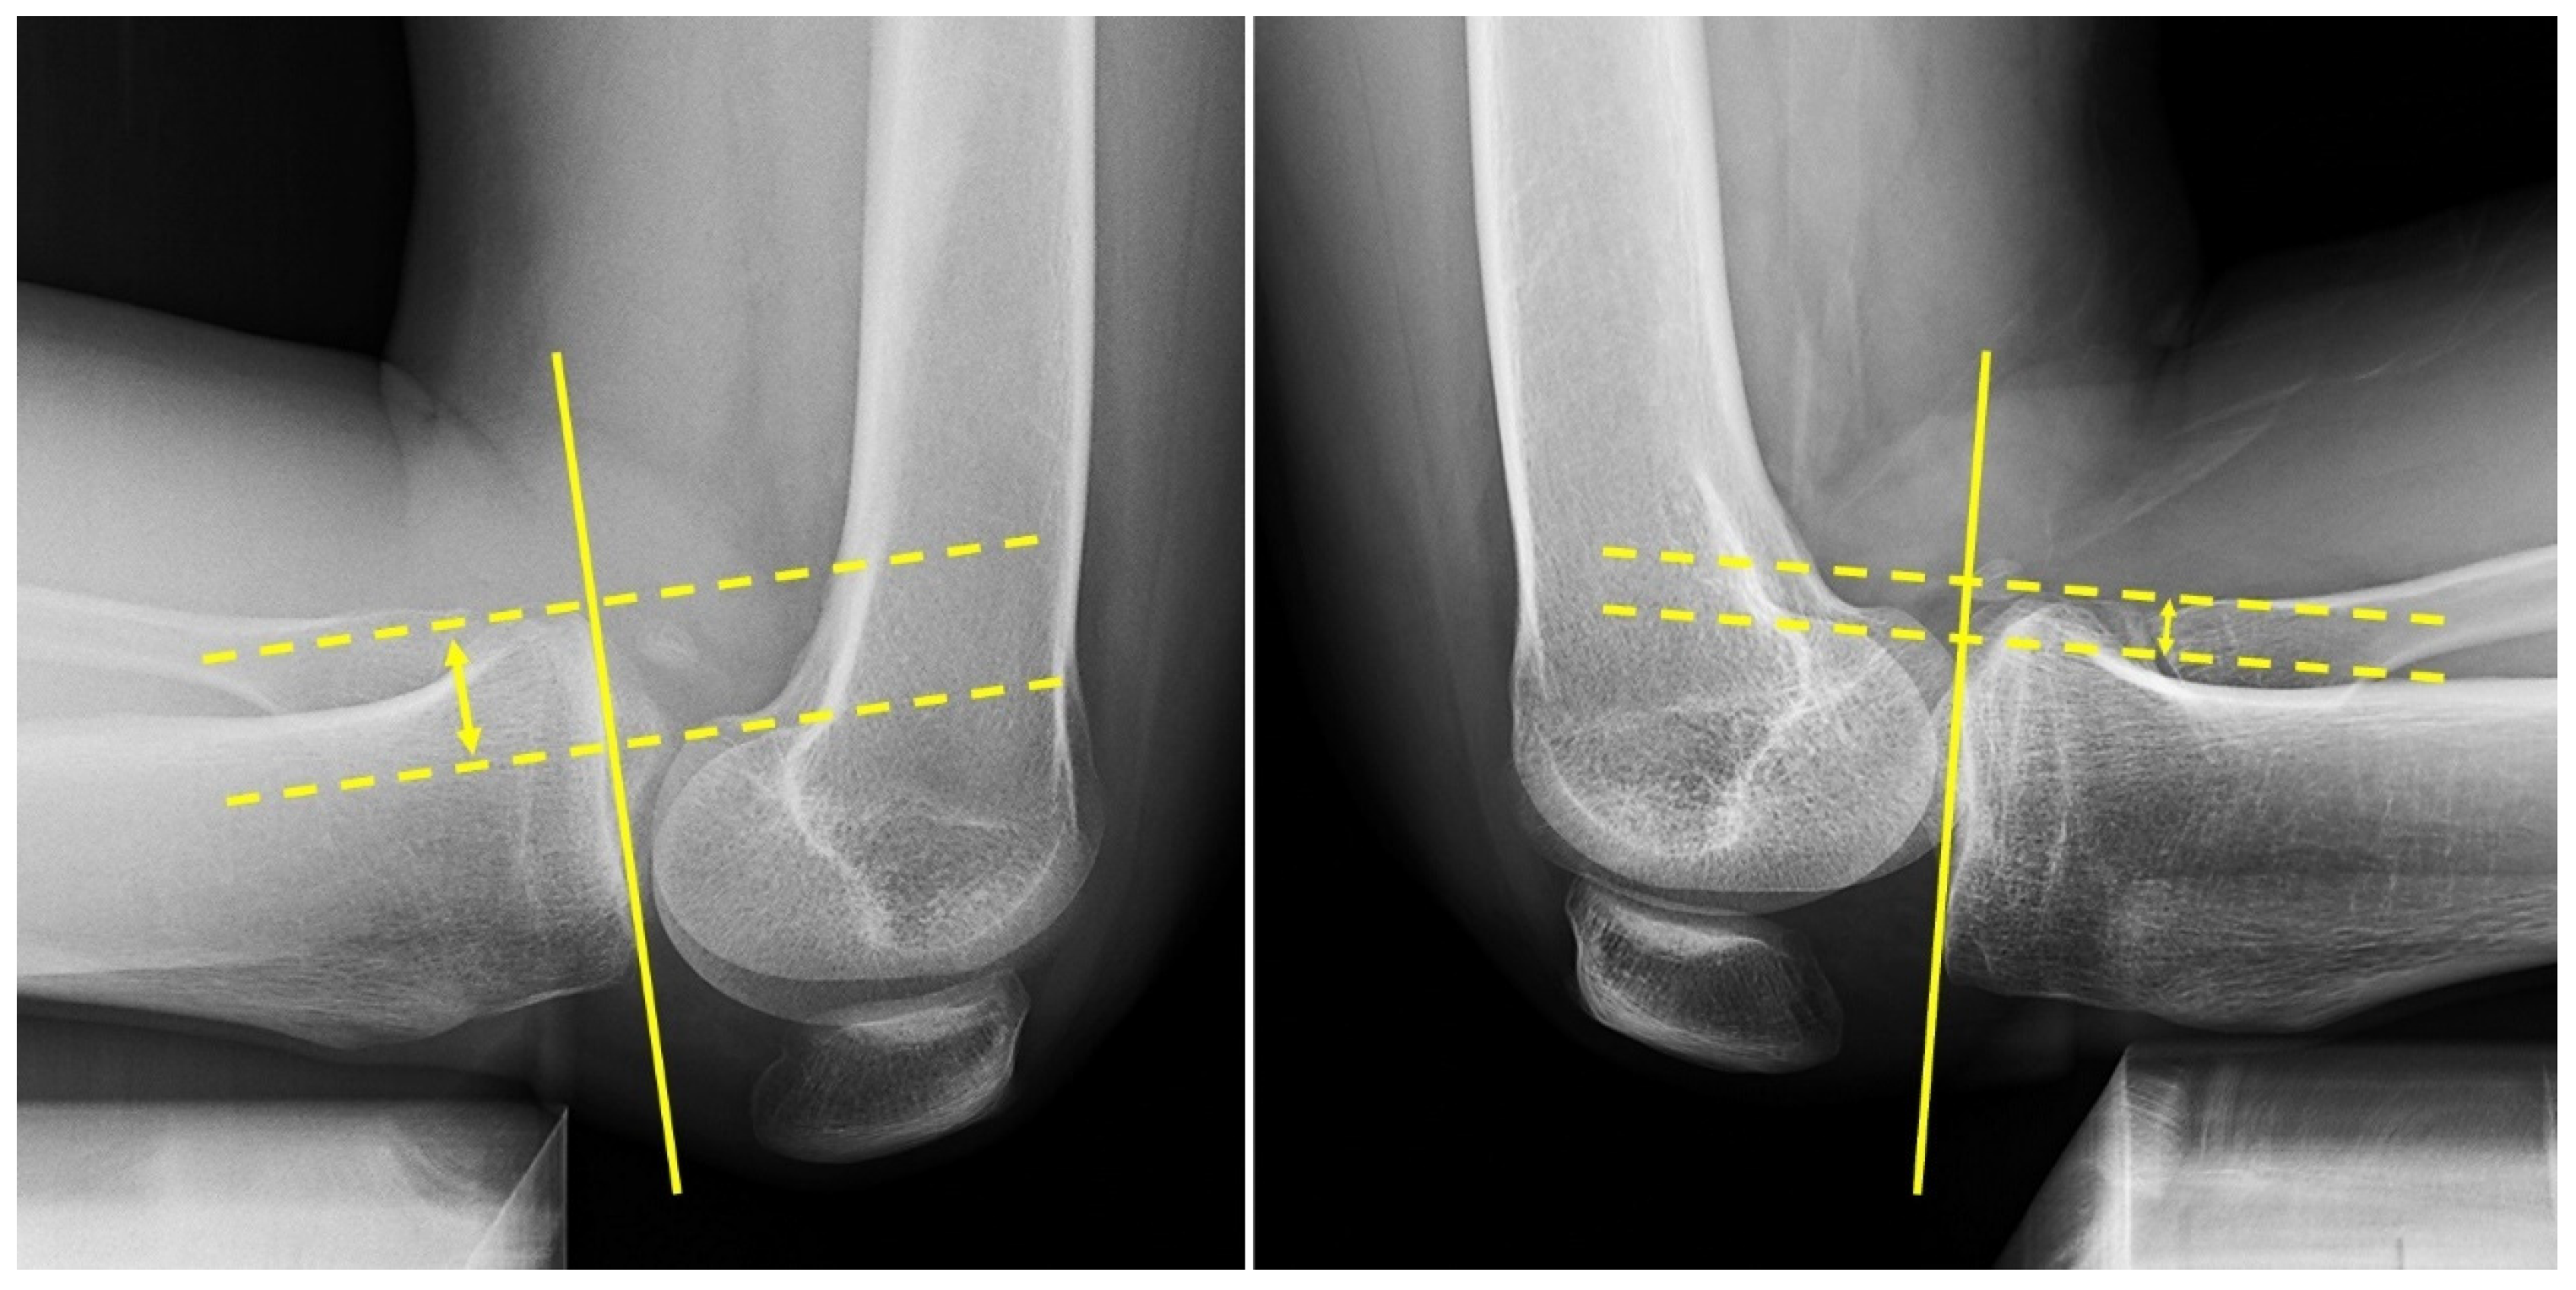

2.4. Evaluation of Tibial Tunnel Position on 3-Dimensional Computed Tomography (3D-CT)

2.5. Patient Demographics, Clinical and Radiologic Measurements, and Complications

3.2. Tibial Tunnel Position on 3D-CT Scan